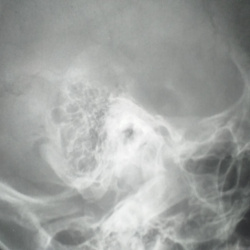

Женщина 30 лет. Встречаю такое впервые. Описал как мастоидит,но сомневаюсь. Анамнеза не знаю,снимки выполнены в поликлинике. Если не мастоидит,то что может быть?